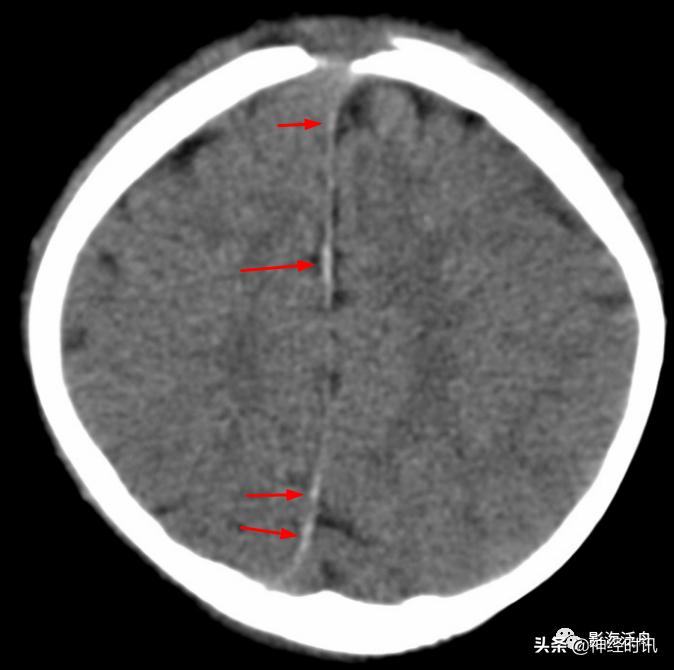

典型的大脑镰前部少量蛛血,血肿的边缘毛糙(红箭)且抵达胼胝体膝部的前缘(黄箭头)。4天后复查头颅CT平扫,相应部位少量蛛血基本吸收。

另一例表现类似的大脑镰前部少量蛛血,血肿的边缘总是有一种毛毛糙糙的感觉(红箭)。